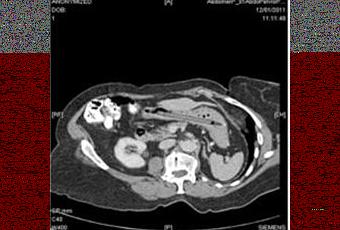

“Una donna di 76 anni è giunta all’osservazione urgente dei medici per perdita di peso e diarrea. Un’indagine sigmoidoscopica ha mostrato una grave diverticolite e una successiva TAC addominale ha messo in evidenza la presenza di un oggetto estraneo di forma allungata nello stomaco, ma nessun’altra anomalia. I sintomi si sono poi risolti spontaneamente. Nel corso della visita la donna si è ricordata di aver ingoiato per sbaglio una penna 25 anni prima. La stava usando per toccare delle placche su una tonsilla quando le è sfuggita e non ha potuto evitare di inghiottirla. E in effetti una gastroscopia ha dimostrato la presenza di una penna con la punta di feltro nello stomaco (cliccare per ingrandire), ma senza evidenze di lesioni gastriche. Il caso è stato poi discusso in un consesso di gastroenterologi che ne hanno consigliato la rimozione nonostante non avesse provocato danni per ben 25 anni al fine di evitare eventuali perforazioni del duodeno. La penna dunque è stata rimossa mediante intervento endoscopico”.